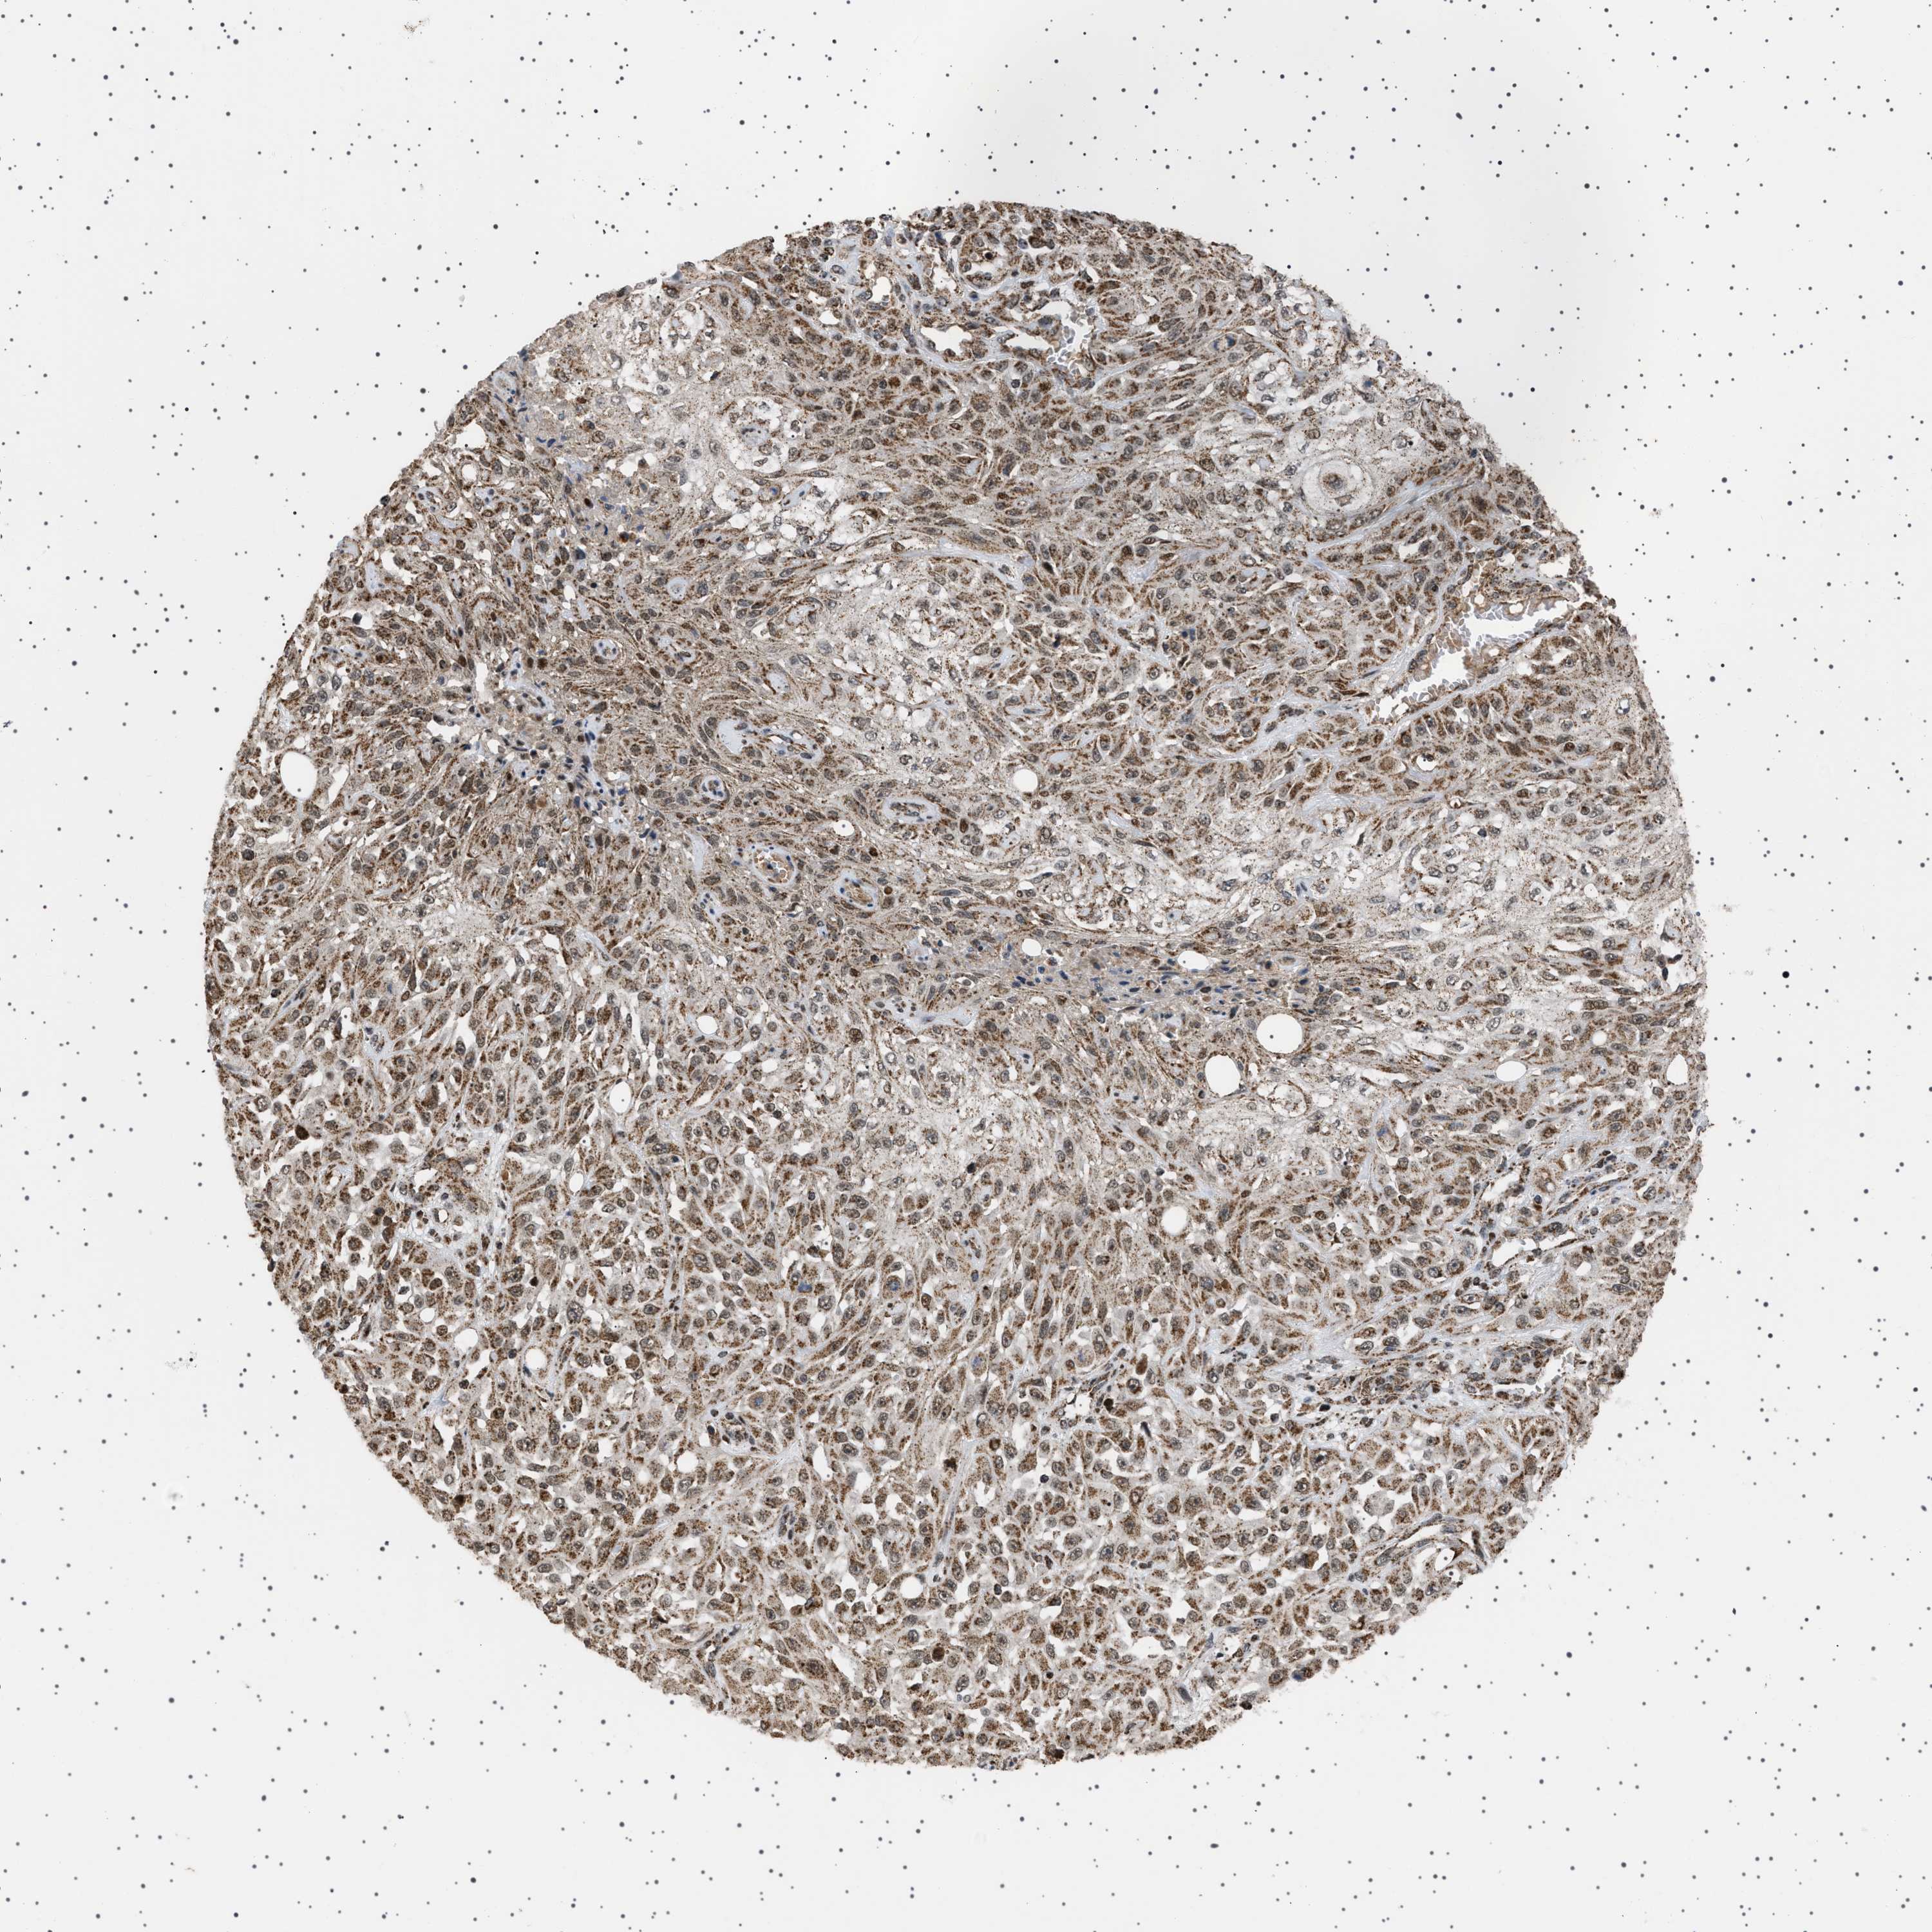

SKIN CANCER - Protein expressioni

A mouse-over function shows sample information and annotation data. Click on an image to view it in a full screen mode. Samples can be filtered based on level of antibody staining by selecting one or several of the following categories: high, medium, low and not detected. The assay and annotation is described here.

Each image is clickable and will lead to virtual microscopy that enables deeper exploration of all samples and also displays staining intensity scores, fraction scores and subcellular localization as well as patient and tissue information for each sample.

Antibody HPA017214

Staining

Medium

Intensity

Moderate

Quantity

75%-25%

Location

Cytoplasmic/membranous,nuclear

Squamous cell carcinoma, NOS